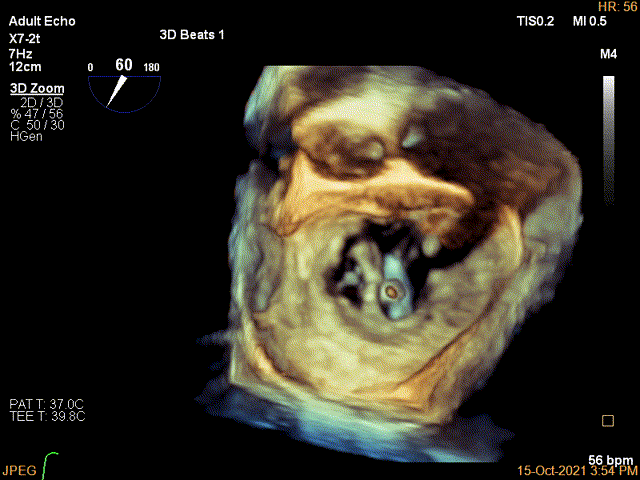

3D确认左房较大,穿刺点位近似于3点位

3D视图下大鞘位置及长度测量

(2)该患者双房明显扩大,空间结构出现了扭转,在Bi-Plane平面LVOT view看不到左室流出道,因此术中通过3D zoom将主动脉瓣旋转到12点钟方向 ,穿刺位置最好为3点钟,自内交界区上方较合适,确定穿刺高度后,左心房3D成像确认。因此,对于这类患者结合3D视图找到最合适的房间隔穿刺点是成功的关键。